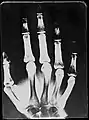

X-Ray image of right hand with no details in the bones at the bottom of the image

Original: X-Ray image of right Hand;

1st. order equidensities after pseudo-solarization of original

colored 1st. order equidensity-series using pseudo-solarization, B&W copies chromogenic developed